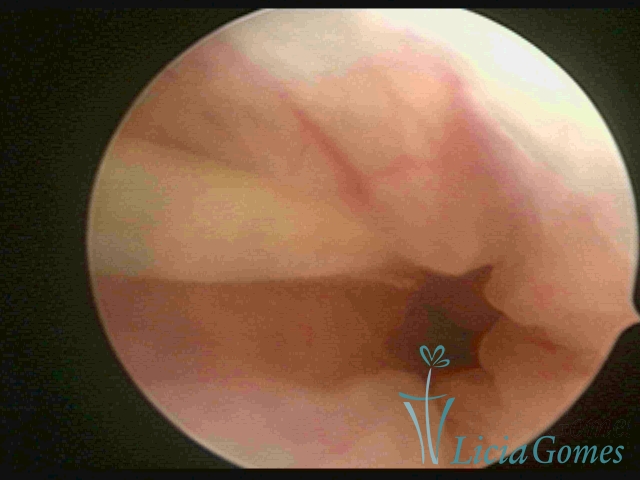

Cavidade uterina com DIU, envelhecido e dobrado